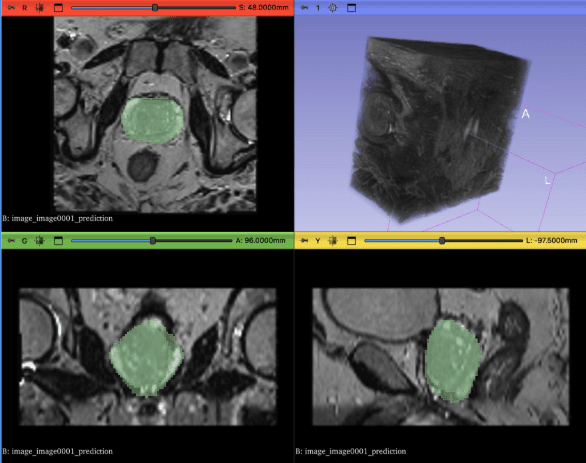

Two-Stage Deep Learning Pipeline for Prostate and Lesion Segmentation in MRI Scans. A pipeline of data processing and two U-Net transformer models that can output prostate and legion segmentation.